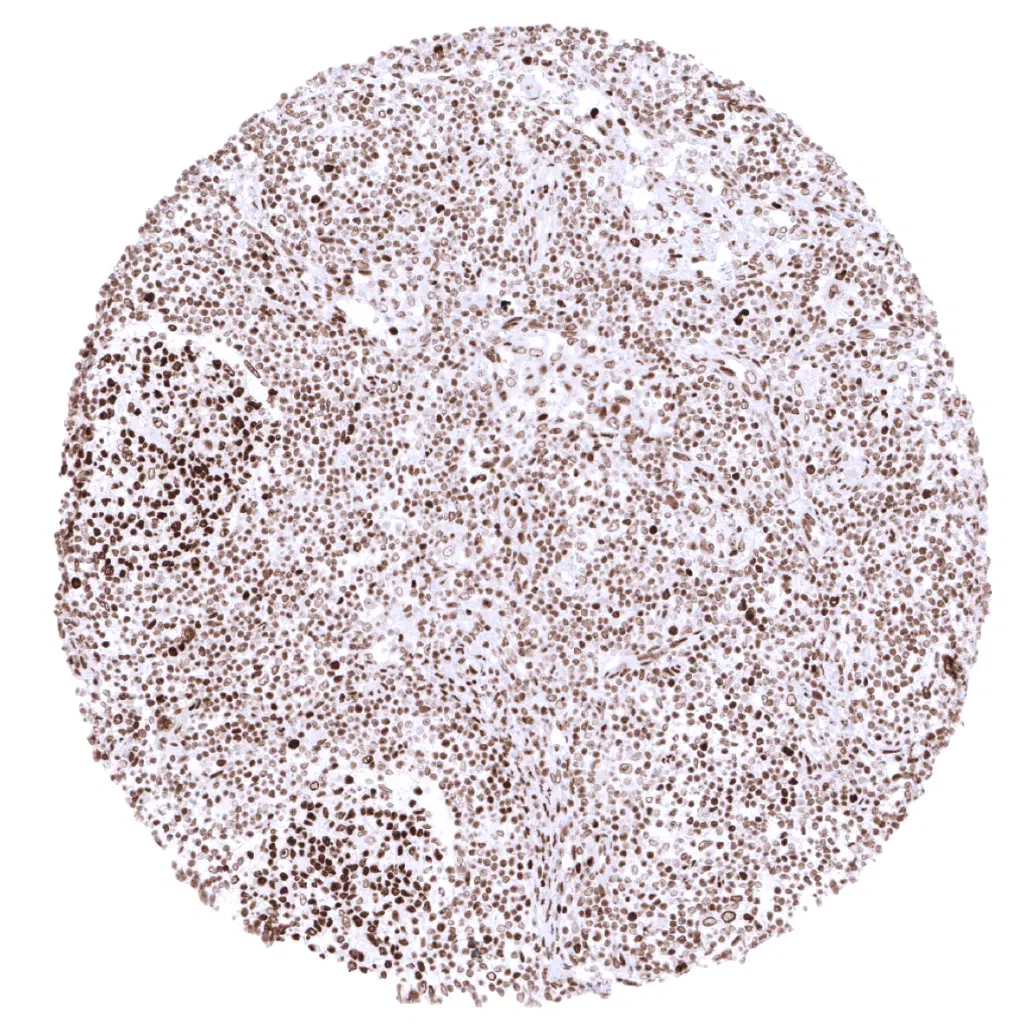

Spleen